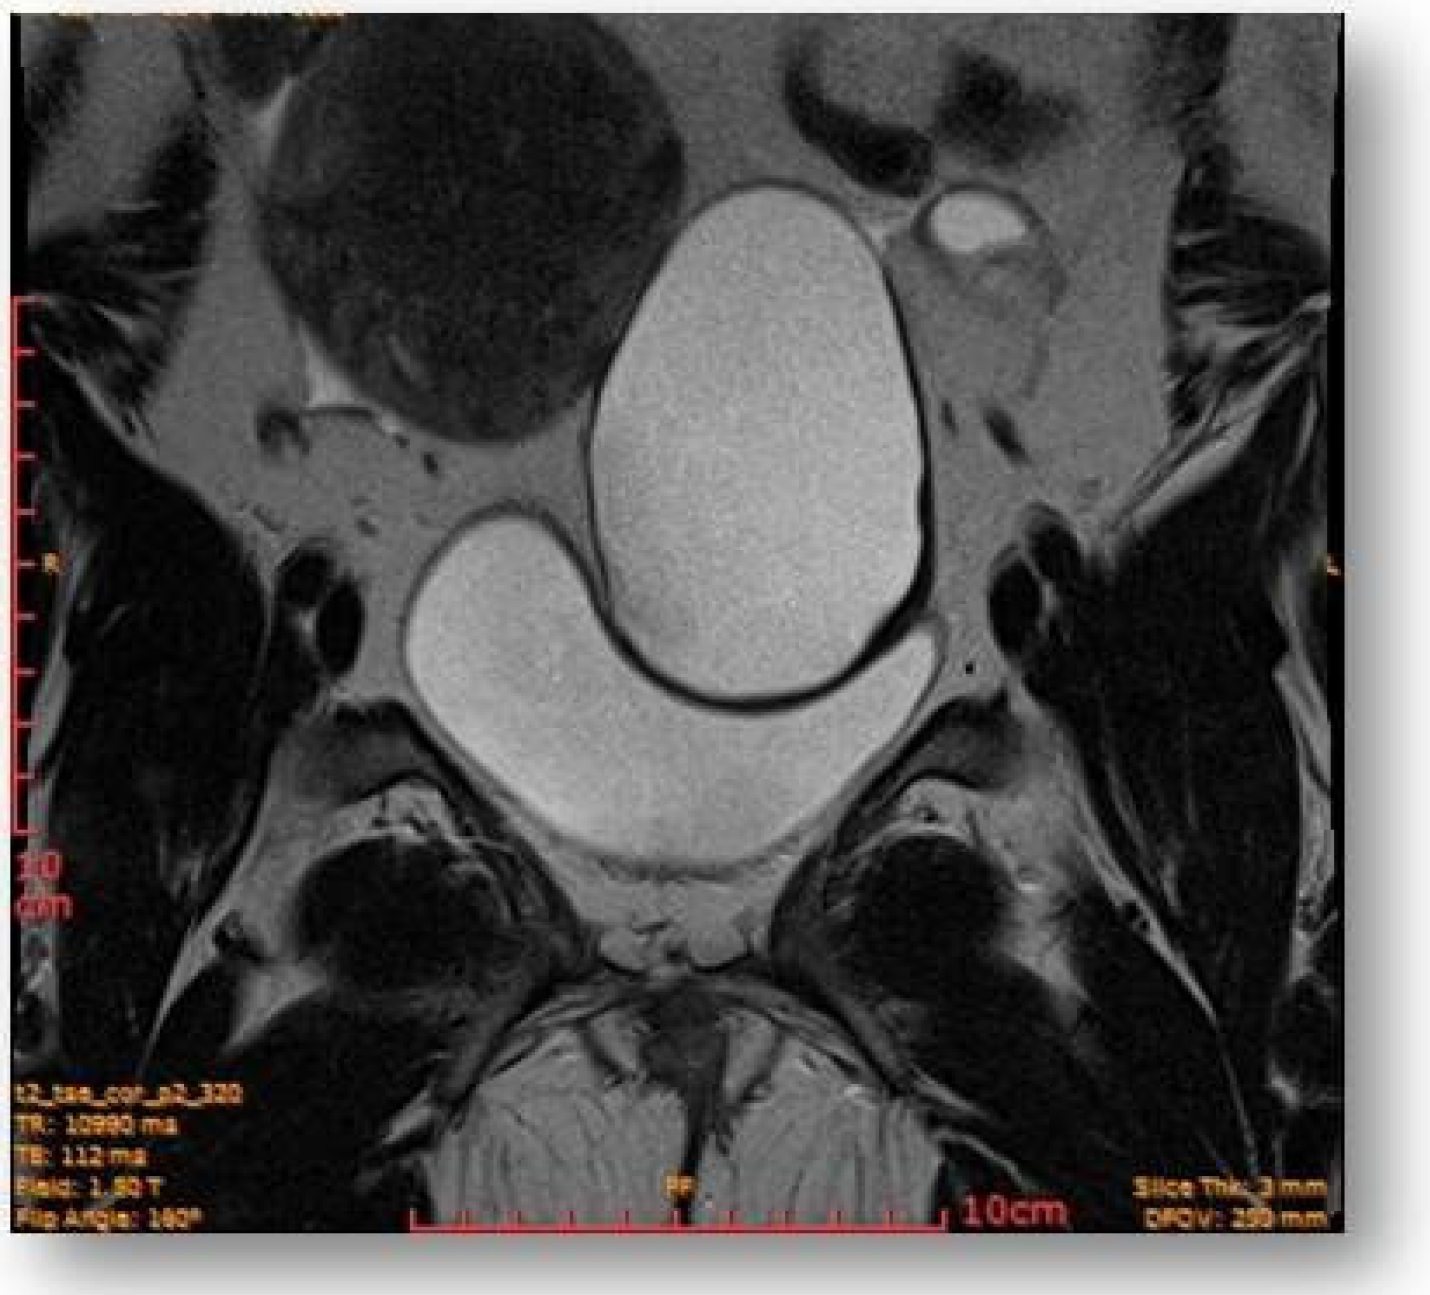

Left parauterine, between the left lateruterine wall and the left ovary, was attached to the anterior contour of the uterine round ligament, and an ovoid cystic lesion of approximately 100/68/50 mm (oblique CC/AP/LL) is evident (Figure 5).

Figure 5.

Left parauterine, between the left lateruterine wall and the left ovary attached to the anterior outline of the round ligament, an ovoid cystic lesion of 100/68/50 mm is evident.

This showed probably proteinaceous fluid content and mildly irregular wall thickness up to ~4–5 mm (on the right lateral contour) and with a mural micronodule of ~5 mm with contrast uptake at the level of the left antero-lateral contour. The appearance advocated the first hypothesis for a “border-line” left paraovarian cyst, with suspicious elements of neoplastic transformation (Figure 6). It presented the following relationships: anteriorly, it imprints the anterior median-paramedian left pelvic wall, posteriorly with the uterine round ligament, urinary bladder, medially (to the right) with the uterus and urinary bladder, laterally (to the left) with the left ovary.

Figure 6.

Ovoid cystic lesion imprints the urinary bladder without invasion into it.